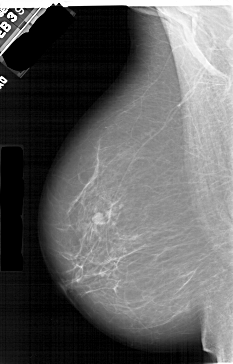

A_1409_1.LEFT_CC

LEFT_CC LINES 6871 PIXELS_PER_LINE 3946 BITS_PER_PIXEL 12 RESOLUTION 43.5 NON_OVERLAY